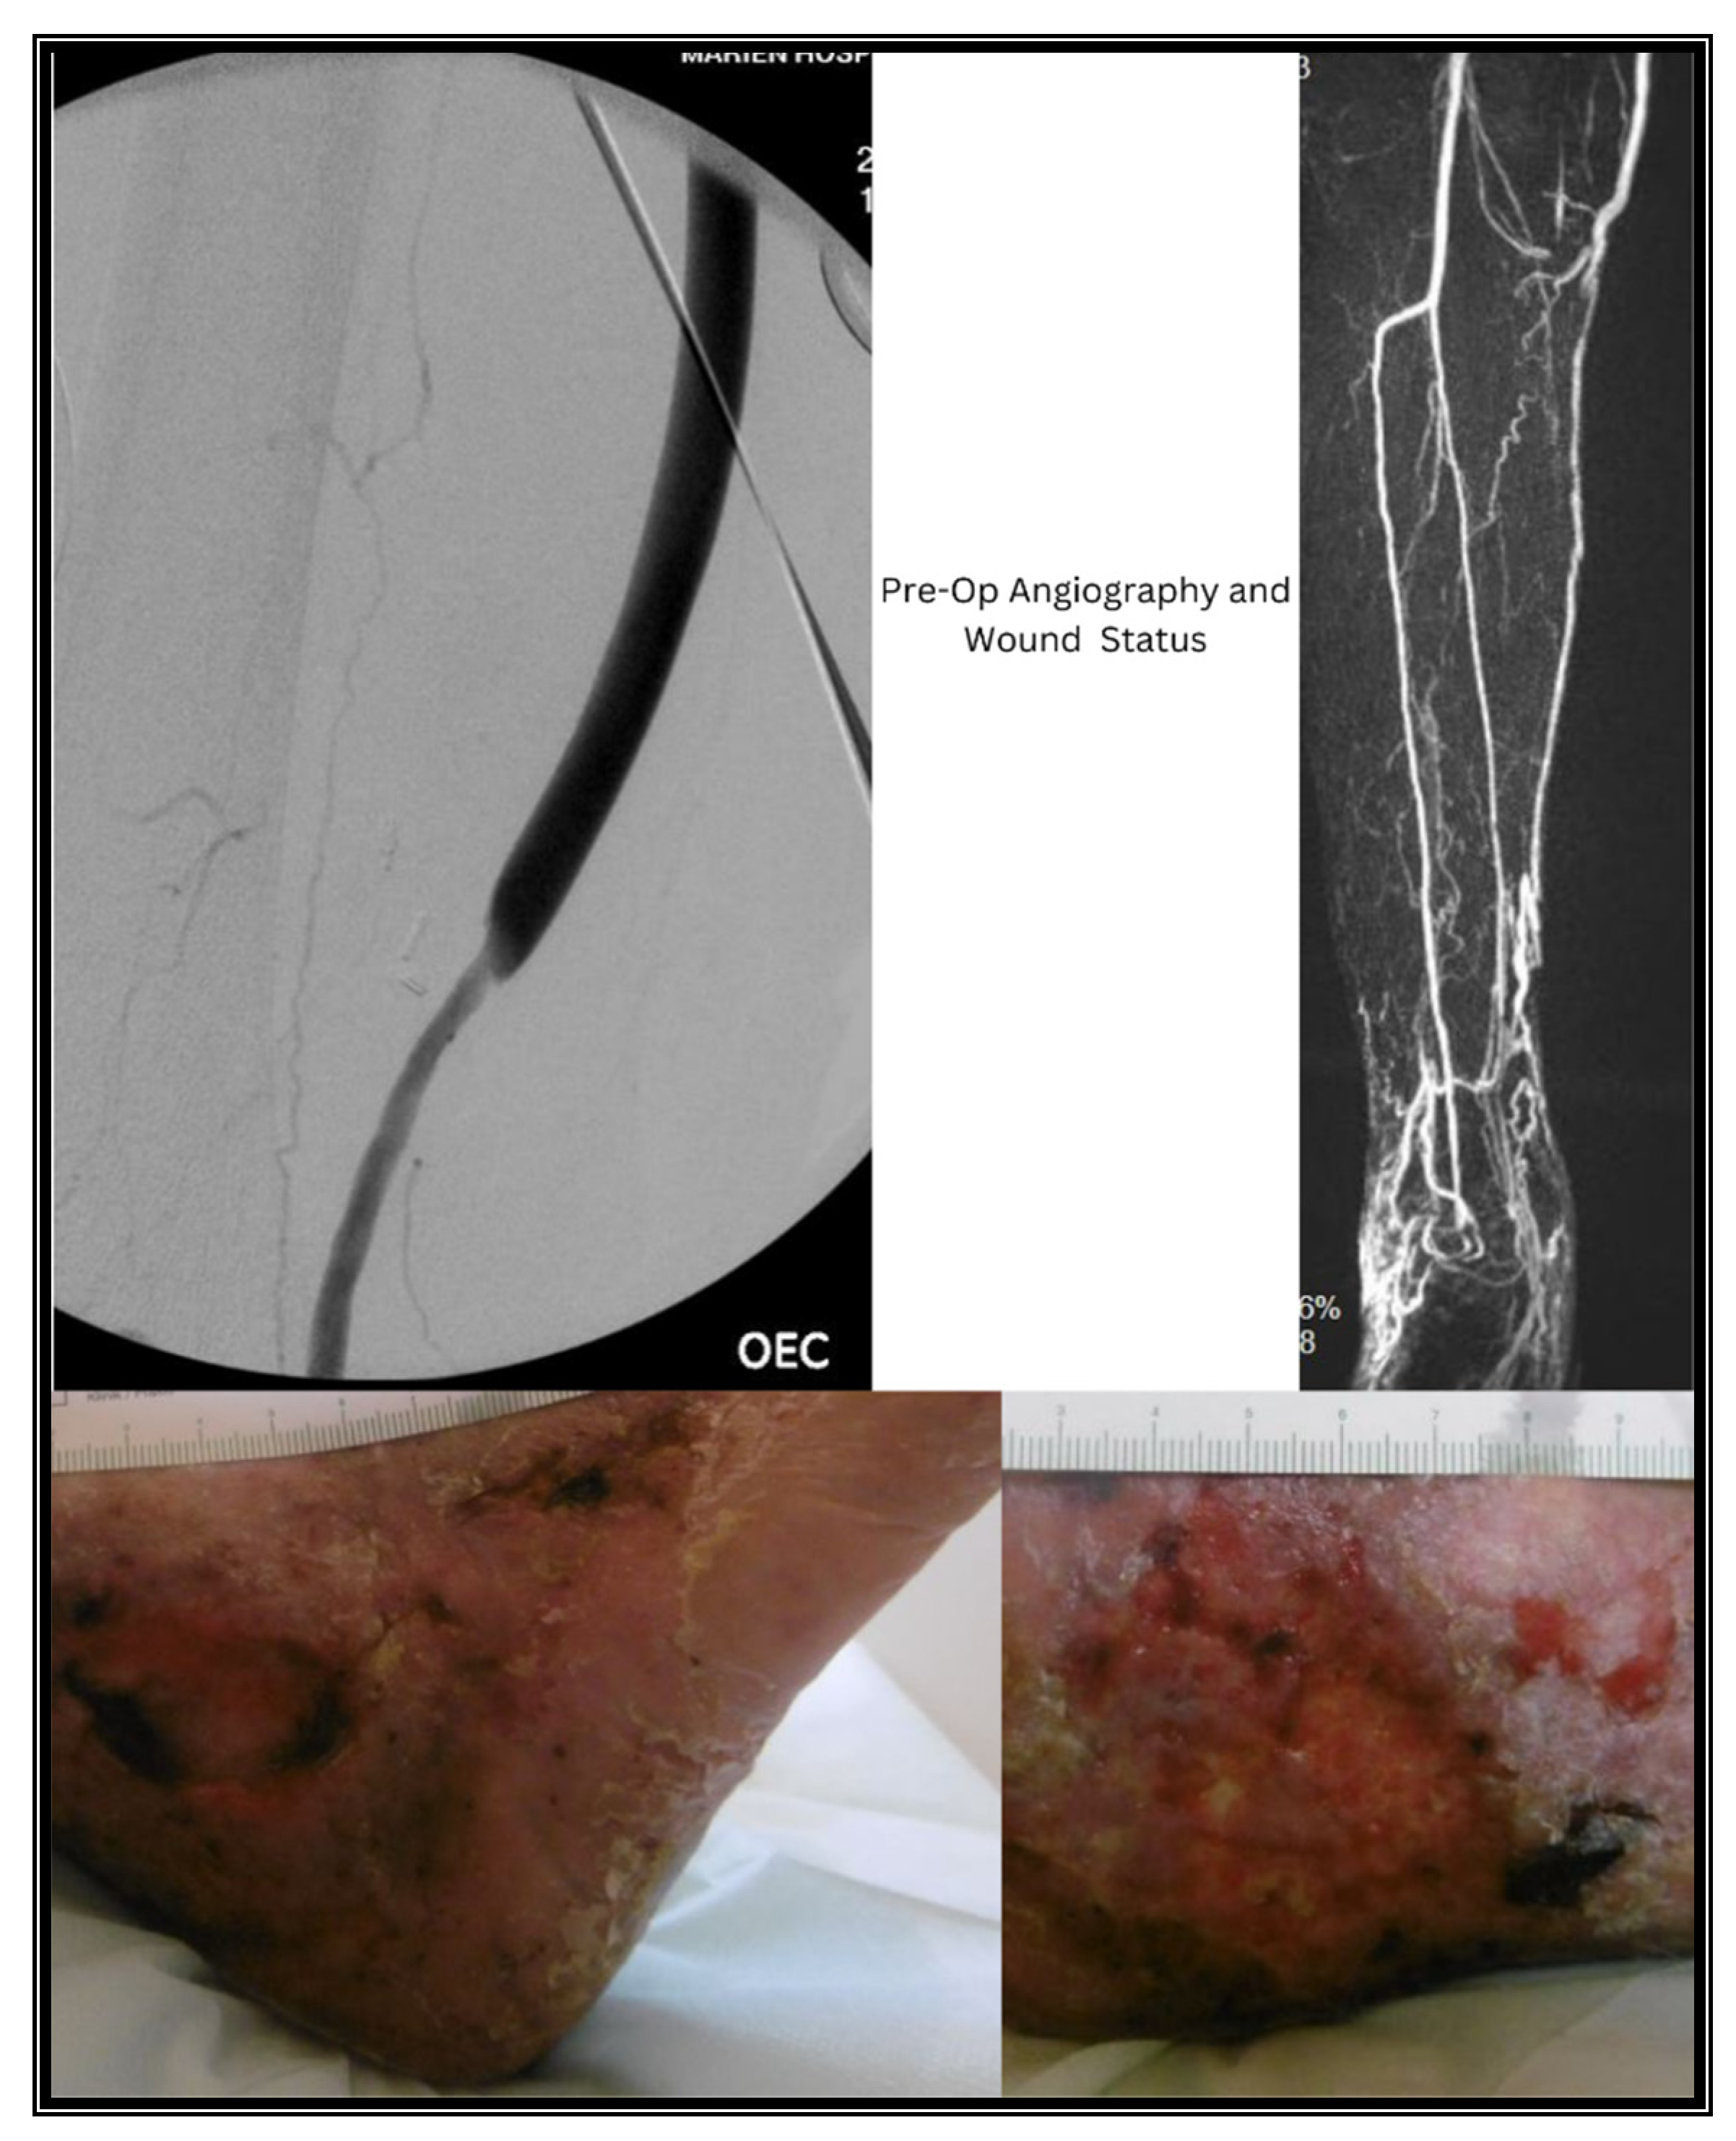

3.1. Case I